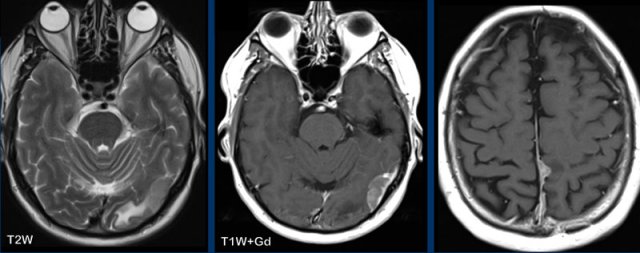

These images are of a 9-year old child who presented with headache.

Images

there is a large cystic posterior fossa mass with compression and

obstruction of the fourth ventricle and brainstem.

A solid contrast enhancing

nodule is present, as well as enhancement of the cyst wall.

Conclusion

Most likely diagnosis at this age is a pilocytic astrocytoma

These images are of a 3-year old child who also presented with headache.

There are two important findings.

Take a closer look at the images and then continue reading.

Large cyst with enhancing nodule in the posterior fossa..

Notice that the wall of the cyst enhances.

The nodule is not located on the pial side (inner part of the meninges) unlike in a hemangioblastoma.

Most likely diagnosis at this age is a pilocytic astrocytoma.

The enhancing wall is part of the tumor and needs to be resected.